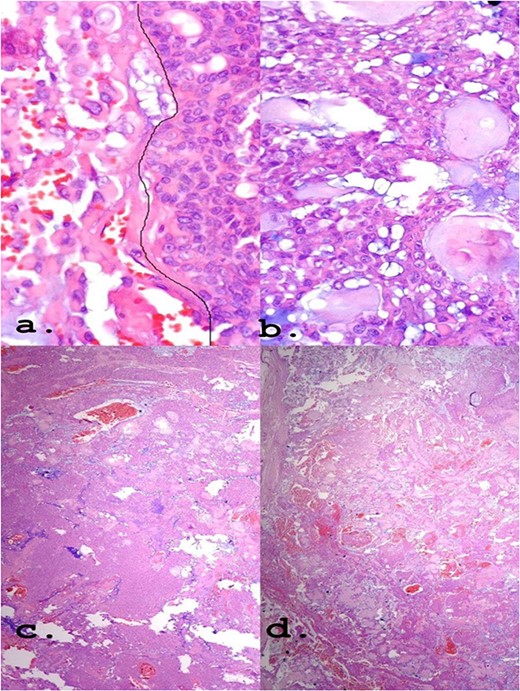

The positivity of markers such as p63, myoepithelial cell markers and AE1/AE3, epithelial cells, found in immunohistochemistry (Fig. 4) may also be present in myoepitheliomas but in a lower percentage, ranging from 17 and 44% [8]. However, in this report, a large number of plasmacytoid epithelial cells and mainly ductal formations are superimposable characteristics of the PA, despite the scarce stromal component and foci of myoepithelium.

Own nuclear marker of myoepithelial cells (a) and (b): p63 ×40 and ×10, respectively. Markers for epithelial cells (c) and (d): CK7 ×10 and Pancytokeratin (AE1–AE3) ×40, respectively.